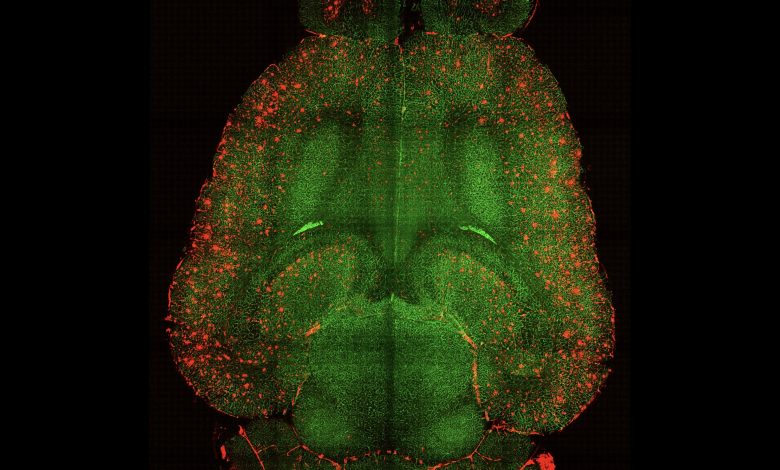

Crédito: Instituto de Bioengenharia da Catalunha (IBEC)